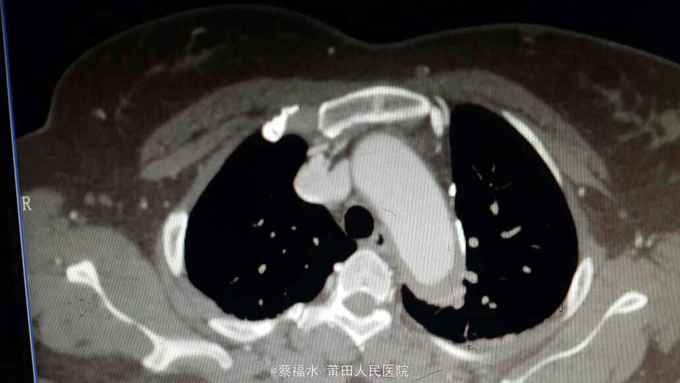

女性患者,56岁,以“上腹部、左腰部突发疼痛2小时”为主诉入院。入院查体:HR70次/分,BP220/105mmHg,双肺呼吸音清,未闻及干湿性啰音,心律齐,各瓣膜区未闻及杂音,腹平软上腹部压痛明显,无反跳痛,胆囊区无压痛,墨菲氏征阴性,肝脾肋下未及,左肾区叩痛可疑阳性,肠鸣音约5次/分。入院后查血淀粉酶正常,肌钙蛋白I阴性,心肌酶谱正常,心电图无心肌缺血改变,上腹部+胸部CT提示:右肾囊肿,余未见明显异常。予抑酸、维生素K3、曲马多等应用后,患者仍腹痛剧烈,性质同前,无明显缓解。予完善胸主动脉、腹主动脉、髂动脉CTA结果如下:

腹主动脉夹层动脉瘤 予控制血压、控制心率等治疗,患者腹痛较前缓解